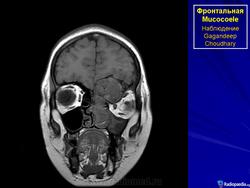

Мукоцеле

Приложения:

3.c.slayd27.jpg4.c.slayd28.jpg